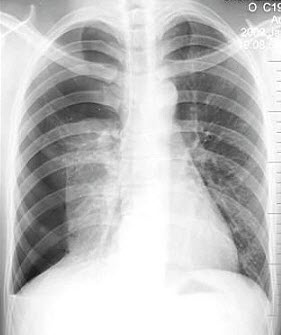

C.胸部斜位

D.胸部前弓位